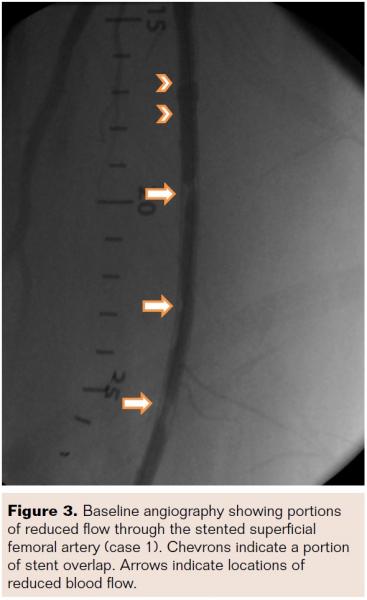

A 74-year-old white male presented with severe claudication (Rutherford class III; TASC A; ABI 0.81) in the right leg. Comorbidities included hypertension, hyperlipidemia, diabetes, coronary artery disease, atrial fibrillation, chronic kidney disease, and smoking history. Stent placement by PTA of the right femoral artery extending from the proximal to distal segments was performed less than 1 year prior. Angiographic imaging revealed a significant reduction in blood flow through the stented SFA (Figure 3). The imaging core laboratory identified a 75% diameter stenosis, a minimum lumen diameter of 1.2 mm within a reference vessel diameter of 4.8 mm. Calcification was not evident and the lesion length was 101 mm with an overall stented length of 220 mm.